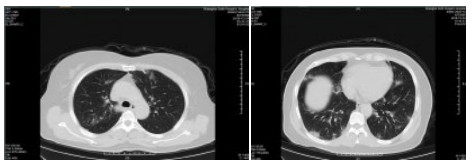

| 图 6 患者,女性,55岁,既往体健,沪籍,无明确武汉流行病学接触史。发热6 d,伴咳嗽,体温39.4℃,伴肌肉酸痛,流感病毒A型IgM阳性,抗柯萨奇病毒IgM阳性,新型冠状病毒核酸检测阴性。肺部CT提示双肺散在磨玻璃结节,部分贴近胸膜。诊断甲型流感病毒性肺炎 Fig 6 Case 6, female, 55 years old, born in Shanghai, was physically healthy, and had no clear history of epidemic exposure of Wuhan. She had fever for 6 days, body temperature was 39.4 ℃, with cough, muscle ache, positive influenza A IgM and anti Coxsackie IgM, negative novel coronavirus nucleic acid test. Lung CT showed ground glass nodules were scattered in bilateral lungs, some of which were close to pleura. She was diagnosed as influenza A virus pneumonia |

| 图 7 患者,女性,36岁,沪籍,有武汉流行病学接触史。发热8 d伴咳嗽,咳痰,有头胀痛,体温38.5℃, 白细胞总数21.8×109/L,淋巴细胞计数10.4%,甲型流感筛查阴性,流感病毒B型IgM阳性,新型冠状病毒核酸检测2次阴性。肺部CT提示双肺多发团片影,实变及磨玻璃结节,伴支气管充气征。诊断乙型流感病毒性肺炎 Fig 7 Case 7, female, 36 years old, born in Shanghai, with a history of epidemic exposure of Wuhan. She had fever for 8 days with cough, expectoration, head pain, body temperature of 38.5℃, total white blood cells of 21.8×109/L, lymphocyte count of 10.4%, negative influenza A virus screening, positive influenza B IgM, and negative novel coronavirus nucleic acid test for twice. Lung CT showed multiple mass shadows, consolidation and ground glass nodule in both lungs, accompanied by bronchiectasis. She was diagnosed as influenza B pneumonia |

| 图 8 患者,男性,20岁,湖北籍,发病前6 d有武汉流行病学接触史,发热,体温39.3℃,有干咳,血白细胞总数及淋巴计数正常,甲型、乙型流感病毒抗原筛查阴性以及其他呼吸道常规病毒筛查阴性,新型冠状病毒核酸检测2次阴性。肺部CT提示左下肺磨玻璃结节,贴近胸膜,可见铺路石征,小叶间胸膜增厚。病因不明 Fig 8 Case 8, male, 20 years old, born in Hubei Province, had a history of epidemic exposure of Wuhan 6 days before the onset of the disease. He had fever with a body temperature of 39.3 ℃, dry cough, normal WBC and lymph count, negative influenza A and B virus screening, and other routine respiratory virus screening, negative novel coronavirus nucleic acid test for twice. Lung CT showed ground glass nodule of the lower left lung, close to the pleura, with paving stone sign and thickening of interlobular pleura. Unknown etiology |